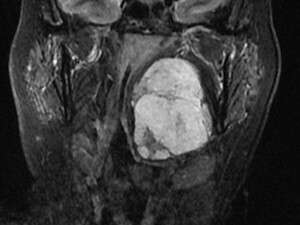

הגידול שהוסר מראשה של האישה. בגודל כדור טניס צילום MRI

הניתוח המקובל לכריתת גידול מסוג זה מצריך חתכים בצוואר ובפנים וניסור הלסת. על כן, אם האישה הייתה מנותחת בדרך המסורתית, הדבר היה מצריך אשפוז ארוך ופגיעה לא פשוטה באיכות החיים של המטופלת.